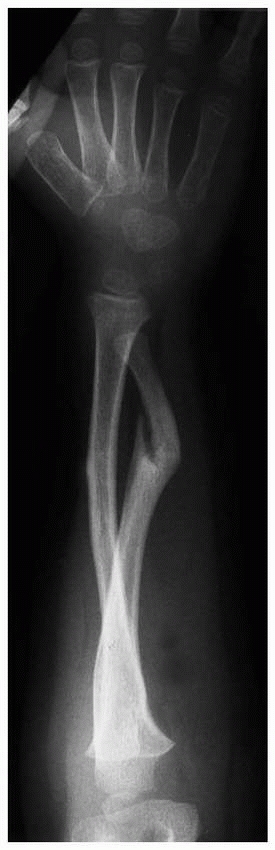

ulnar physeal fractures occur in association with radial metaphyseal or

involves an ulnar physeal fracture rather than a soft tissue disruption

of the distal radioulnar joint. Another ulnar physeal fracture is an

![]() |

FIGURE 9-31 A,B. A 10-year-old boy sustained a closed Salter-Harris type I separation of the distal ulnar physis (arrows) combined with a fracture of the distal radial metaphysis. C. An excellent closed reduction was achieved atraumatically. D. Long-term growth arrest of the distal ulna occurred.